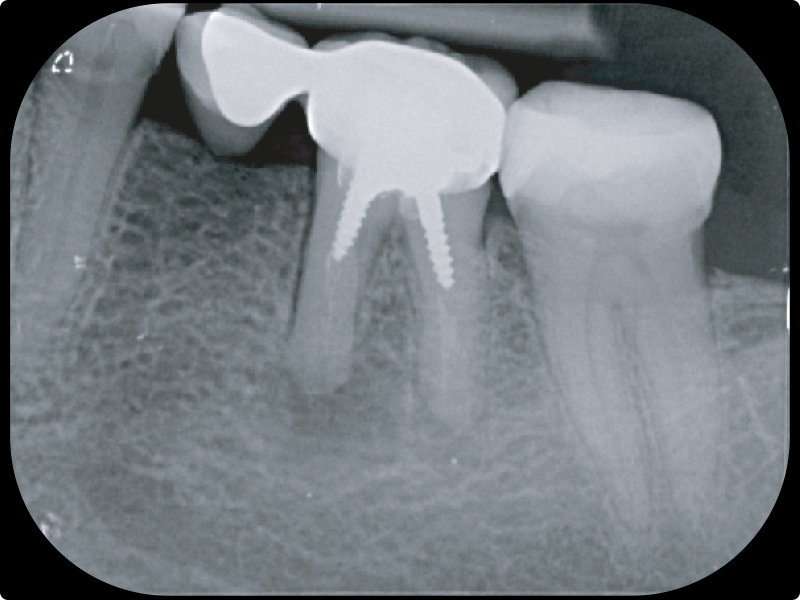

• L’otturazione canalare con i cementi bioceramici:

• materiali

• tecnica

• vantaggi clinici